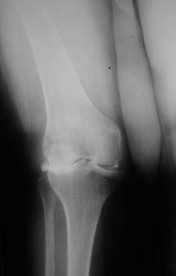

is the radiograph of a 68-year-old woman who has right knee pain that is limiting her activity and severe preoperative valgus deformity. During total knee arthroplasty, what pathologic features are typically encountered?

Explanation

In patients with severe valgus deformity, problems frequently encountered include looseor attenuated medial collateral ligament, tight lateral retinaculum and lateral ligamentous structures (lateral collateral,posterolateral corner), atrophic lateral femoral condyle, lateral patella tracking, and external rotation of the tibia relative to the femur. The hypoplastic lateral condyle can cause internal rotation of the anteroposterior cutting block if the posterior condyler line is used for rotational alignment. The medial soft tissues are typically attenuated and stretched. PREFERRED RESPONSE: 1